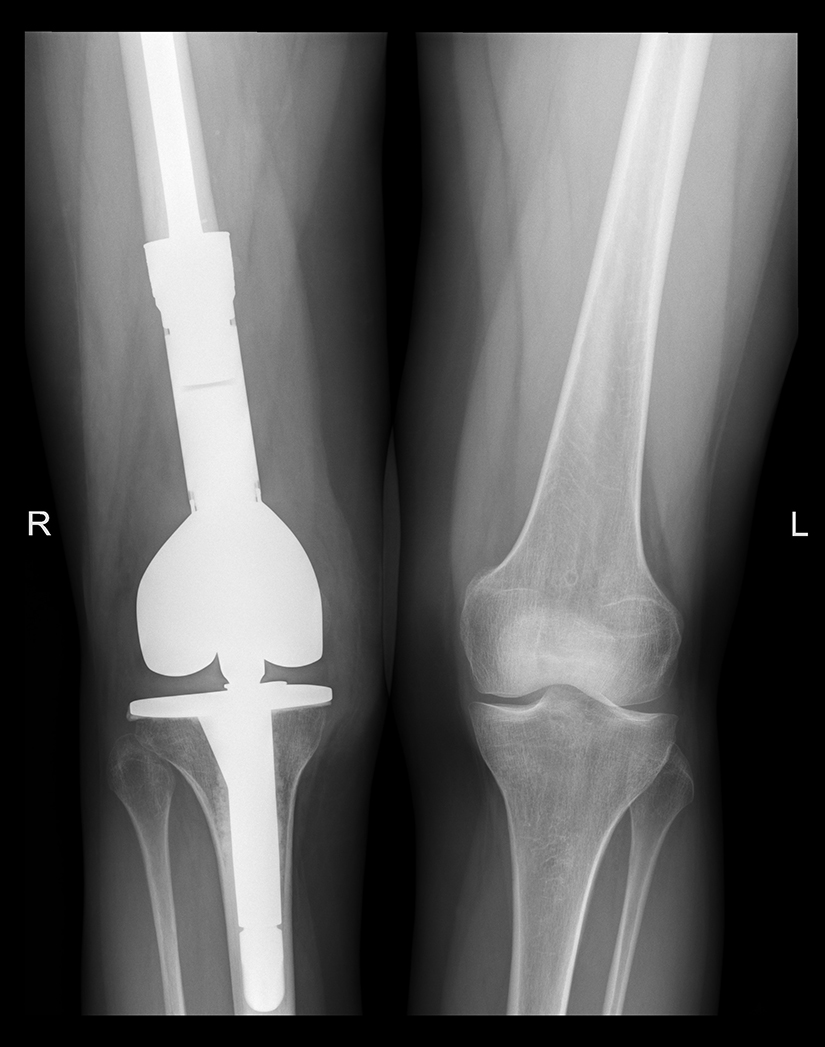

Radiografia arata un osteosarcom telangiectatic in portiunea distala a femurului dupa citostatice

Rezecabilitatea tumorii a fost reevaluata imagistic dupa chimioterapie si dupa aproximativ 3 luni s-a efectuat interventia chirurgicala de rezectie radicala a femurului distal si reconstructie cu artroplastie cu proteza tumorala. Operatia a durat aproximativ 3,5 ore si a fost efectuata de catre o echipa multidisciplinara, avand in componenta sa medici ortopezi si chirurgi vasculari. Procedura de salvare a membrului inferior a fost o operatie complexa si a necesitat rezectia a 15 cm din extremitatea distala a femurului impreuna cu tesutul muscular peritumoral, urmata de inlocuirea acestora cu un modul metalic special (proteza tumorala modulara) si reconstructia genunchiului.